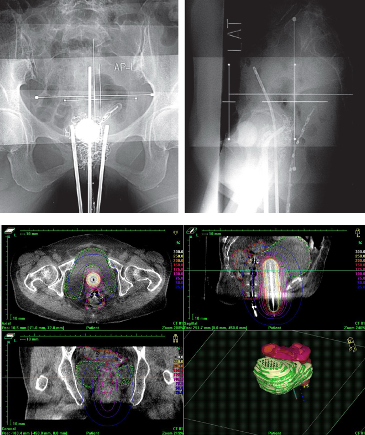

従来は2方向からのレントゲン撮影による2次元治療計画が行われていましたが、現在、当院ではアプリケーターを挿入したままCT画像を撮影できます。この画像を使って、3次元治療計画を行うI G B Tを実施しています。

組織内照射とは、腫瘍の内部やその周囲に専用の細いニードル(径約2mm)をCT画像誘導下に直接刺入し、そのニードルを通して放射線を照射する治療法です。

近年、通常の腔内照射に組織内照射を併用するハイブリッド腔内照射と呼ばれる照射方法が普及してきています。

当院は県内で唯一、このハイブリッド腔内照射を施行可能な施設です。